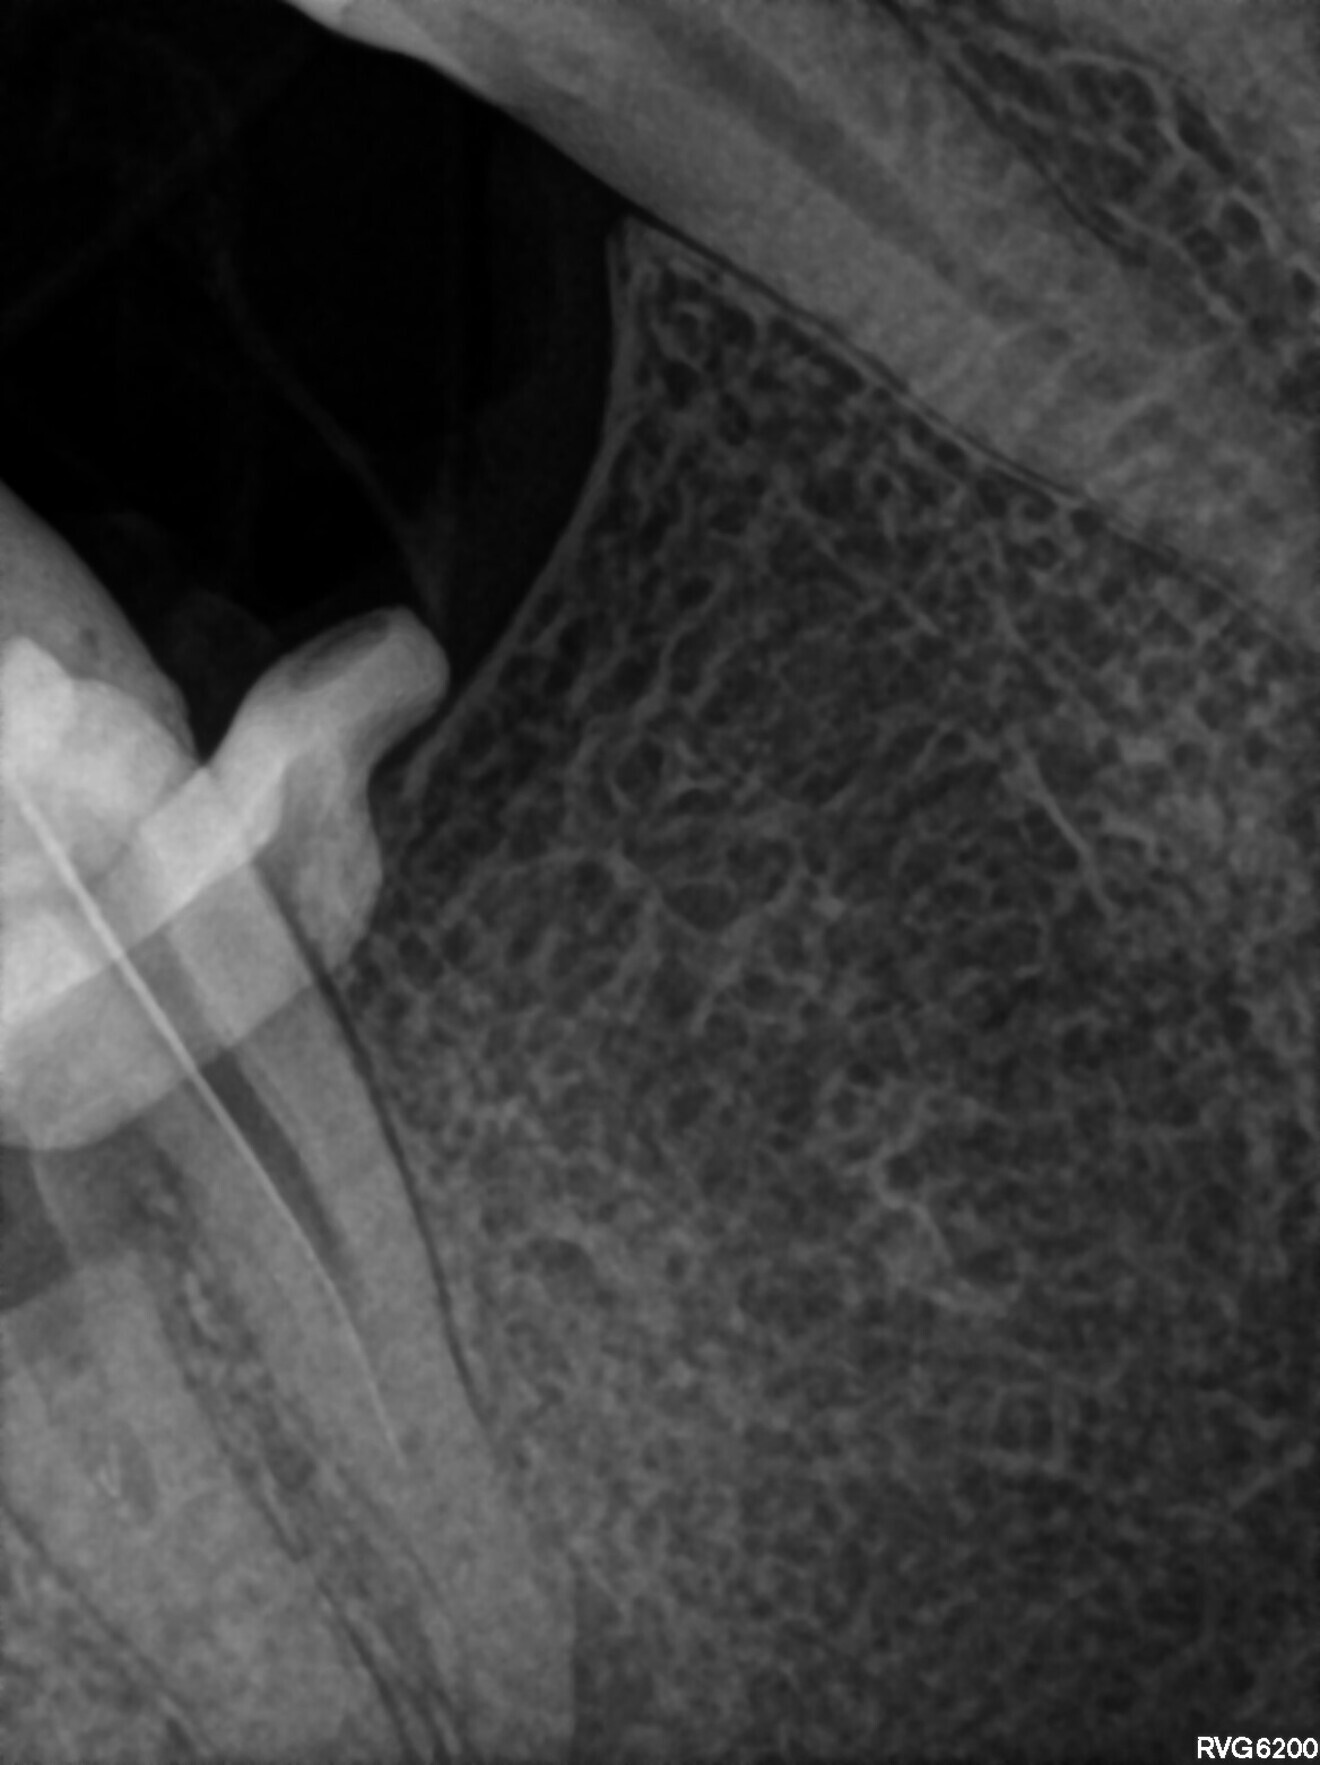

The patient was scheduled for the first appointment to remove the lentulo and scout the canals. After local anaesthesia and placement of the dental dam, the restoration was removed. In the orifices of all three root canals, Endomethasone N was present. This cement was removed with a U-file ultrasonic tip and sodium hypochlorite 5,25%. The tip of the lentulo was exposed. Unfortunately, the lentulo had broken not in the cement but in an unprepared part of canal, which probably had had vital pulp on the day of the treatment because the entire lentulo fragment was surrounded by calcified tissue and was hidden behind the coronal curvature. At this level, the decision was made to use constant flow of sodium hypochlorite 5,25% and laser activation for 10–15 minutes. The calcified tissue was dissolved, and the lentulo was removed. A periapical radiograph was performed to confirm that the entire fragment had been retrieved (Fig. 17). Owing to the gag reflex, this procedure was very difficult. After removing the broken instrument, 17% EDTA and sodium hypochlorite 5,35% was activated with SkyPulse in AutoSWEEPS mode in a few 15- to 20-second cycles, and patency was checked with a hand file. The periapical radiograph revealed that the file engaged deeper than the predicted length of the previous root canal filling (Fig. 18). The tooth was closed with a temporary composite restoration, and the patient was scheduled for a second appointment.